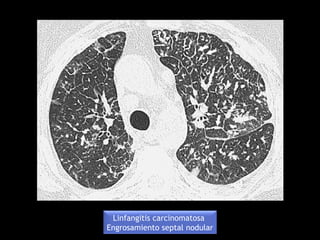

Linfangitis carcinomatosa

Engrosamiento septal liso

Engrosamiento septal nodular